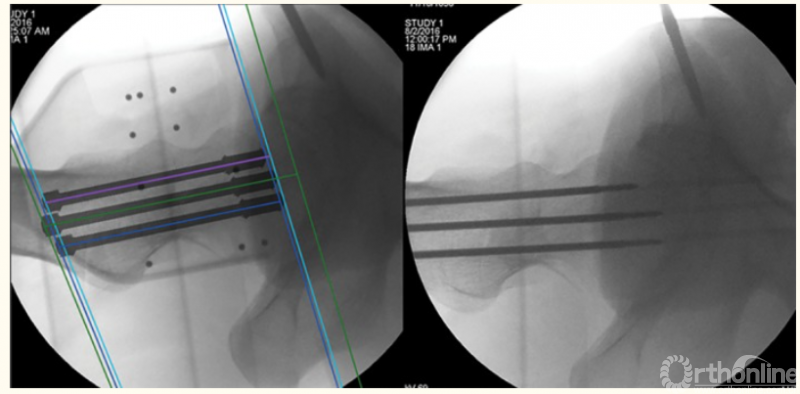

3、股骨颈骨折的机器人辅助手术